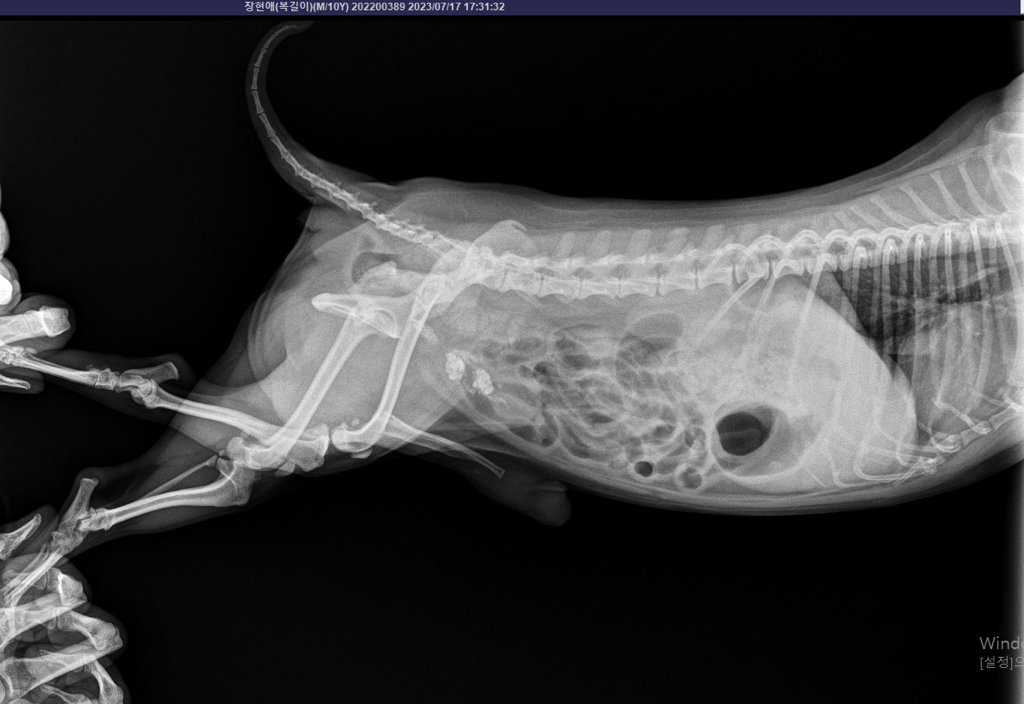

요로결석 검사 받았는데 이게 결석인가요?

4월초 요로결석 수술을 크게했어요.

오늘 다시 결석 검사를 했는데 결석 같아보이는게

찍혔어요.

선생님은 뭔지 정확히 모르지만 결석 같아

보인다고 하시고

하부 요로계 부위에 음영이 관찰되는 것으로 보아 결석의 가능성이 있어보입니다.

해부학적 위치가 방광의 위치이기 때문에 방광의 결석일 가능성이 높아 보이지만 정확한 점은 초음파 검사를 통해 확인해야 합니다.